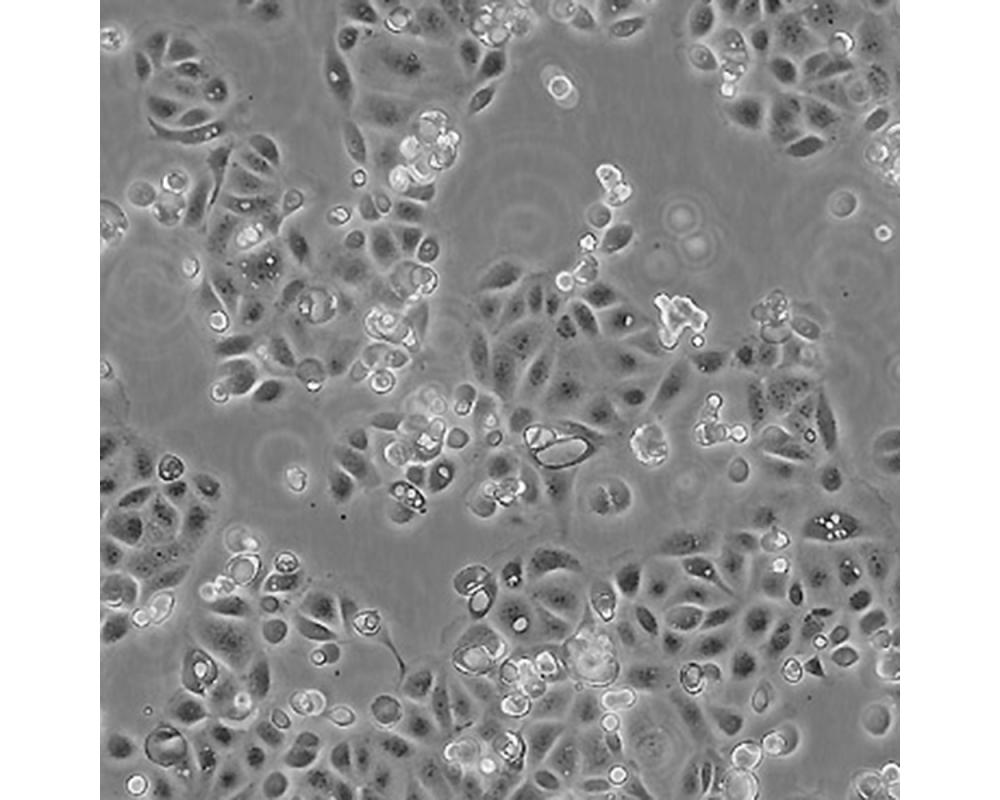

SW1990

產品名稱 SW1990

中文名稱 人胰腺癌細胞

組織來源 胰腺癌;男性

生長特性 貼壁

細胞污染 HIV-1、 HBV、HCV、支原體、細菌、酵母和真菌檢測陰性。

培養基 L15,90%;FBS,10%;雙抗。

傳代方法 1:2-1:4

培養條件 Atmosphere: Air, 95%; CO2, 5%。Temperature: 37℃

細胞傳代步驟 如果細胞密度達80%-90%,即可進行傳代培養。1. 棄去培養上清,用不含鈣、鎂離子的PBS潤洗細胞1-2次。2. 加2ml消化液(0.25%Trypsin-0.53mM EDTA)于培養瓶中,置于37℃培養箱中消化1-2分鐘,然后在顯微鏡下觀察細胞消化情況,若細胞大部分變圓并脫落,迅速拿回操作臺,輕敲幾下培養瓶后加少量培養基終止消化。3. 按6-8ml/瓶補加培養基,輕輕打勻后吸出,在1000RPM條件下離心4分鐘,棄去上清液,補加1-2mL培養液后吹勻。4. 將細胞懸液按1:2到1:5的比例分到新的含8ml培養基的新皿中或者瓶中。

復蘇細胞步驟 將含有1mL細胞懸液的凍存管在37℃水浴中迅速搖晃解凍,加入4mL培養基混合均勻。在1000RPM條件下離心4分鐘,棄去上清液,補加1-2mL培養基后吹勻。然后將所有細胞懸液加入培養瓶中培養過夜(或將細胞懸液加入10cm皿中,加入約8ml培養基,培養過夜)。第二天換液并檢查細胞密度。

細胞凍存步驟 待細胞生長狀態良好時,可進行細胞凍存。下面T25瓶為例;? 1.細胞凍存時,棄去培養基后,PBS清洗瓶底1-2次后加入1ml胰酶,細胞變圓脫落后,加入2ml完全培養基終止消化,可使用血球計數板計數。 2.1000RPM離心5分鐘去掉上清。用血清重懸浮,加DMSO至最終濃度為10%。加入DMSO后迅速混勻,按每1ml的數量分配到凍存管中,注意凍存管做好標識。本公司按每個凍存管細胞數目大于1X106個細胞凍存。3.將凍存管置于程序降溫盒中,放入-80度冰箱,至少2個小時以后轉入液氮灌儲存。記錄凍存管位置以便下次拿取。

細胞凍存 Freeze medium: FBS/NBS, 92%;DMSO, 8%(for reference)Storage temperature: liquid nitrogen vapor phase

細胞運輸 干冰運輸(2ml凍存管)或活細胞運輸(T25細胞瓶)